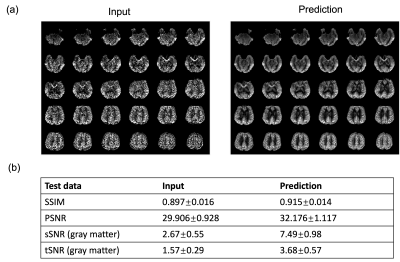

Figure 2 shows the results for the first test dataset, the image for the DL prediction has improved SNR compared to the input. The similarities metrics are also consistent with the visual quality, SSIM and PSNR after DL denoising were improved by 2% and 7.6%, while spatial and temporal SNR were improved by 181% and 134% respectively. Figure 3 shows the results for the second dataset, SSIM and PSNR were improved by 1.4% and 3.9%, while spatial and temporal SNR were improved by 71% and 42% respectively. Figure 4 shows the results for the multi-delay dataset. DL prediction has improved the SNR for perfusion images at each PLD, and improved SNR for the fitted CBF and ATT maps. Figure 5a shows that the global CBF values calculated from the DL prediction is highly consistent with those from the single-delay input images. Figure 5b and 5c show that the fitted CBF and ATT values from the DL predicted multi-delay perfusion images are also consistent with those fitted from the input images.

Figure 2. The input and prediction on the test dataset (same cohort as the training data). (a) Input perfusion image and the DL denoised perfusion image of one subject. The DL denoised image has higher SNR compared to the image. (b) The quantitative results of the input and DL-predicted image. DL denoised image has higher SSIM and PSNR compared to the input image, as well as higher spatial and temporal SNR.

Figure 3. The input and prediction on the second test dataset (A different cohort from the training data). (a) Input perfusion image and the DL denoised perfusion image of one subject. The DL denoised image has higher SNR compared to the image. (b) The quantitative results of the input and DL-predicted image. DL denoised image has higher SSIM and PSNR compared to the input image, as well as higher spatial and temporal SNR.